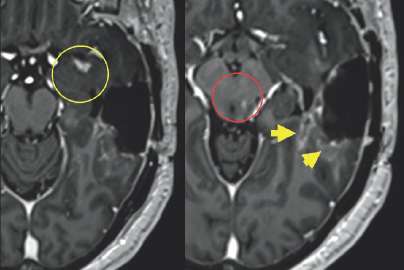

Initially, after the treatment, there was no obvious progression in his symptoms, but by mid-May of that same year, there was a dramatic decline in his condition (Fig. 2.4–2.7). Several concerning transient symptoms appeared, including confusion, lethargy, and significant memory loss, which impacted his compliance with his treatments and caused him to sometimes forget his regimen.

(Left) Dark blue, gray, green, light blue, orange, red, and yellow colors are scattered within a black boarder. A white arrow points to a small light blue blob on the right side of the image. (Right) Dark blue, gray, green, light blue, orange, red, and yellow colors are scattered within a black boarder. A white arrow points to a small red blob on the right side of the image.

FIGURE 2.7 Brain MRI after surgery. Further exploration with advanced perfusion MRI shows a small focus of slightly increased cerebral blood volume (white arrow) which suggests that the majority of the abnormal enhancement is related to post-treatment changes with a small focus of residual tumor.